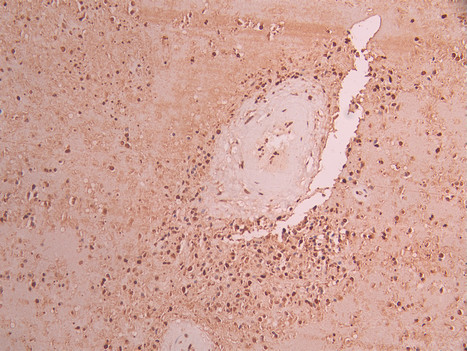

IHC image of CSB-RA552120A0HU diluted at 1:100 and staining in paraffin-embedded human glioma cancer performed on a Leica BondTM system. After dewaxing and hydration, antigen retrieval was mediated by high pressure in a citrate buffer (pH 6.0). Section was blocked with 10% normal goat serum 30min at RT. Then primary antibody (1% BSA) was incubated at 4°C overnight. The primary is detected by a Goat anti-rabbit polymer IgG labeled by HRP and visualized using 0.05% DAB.